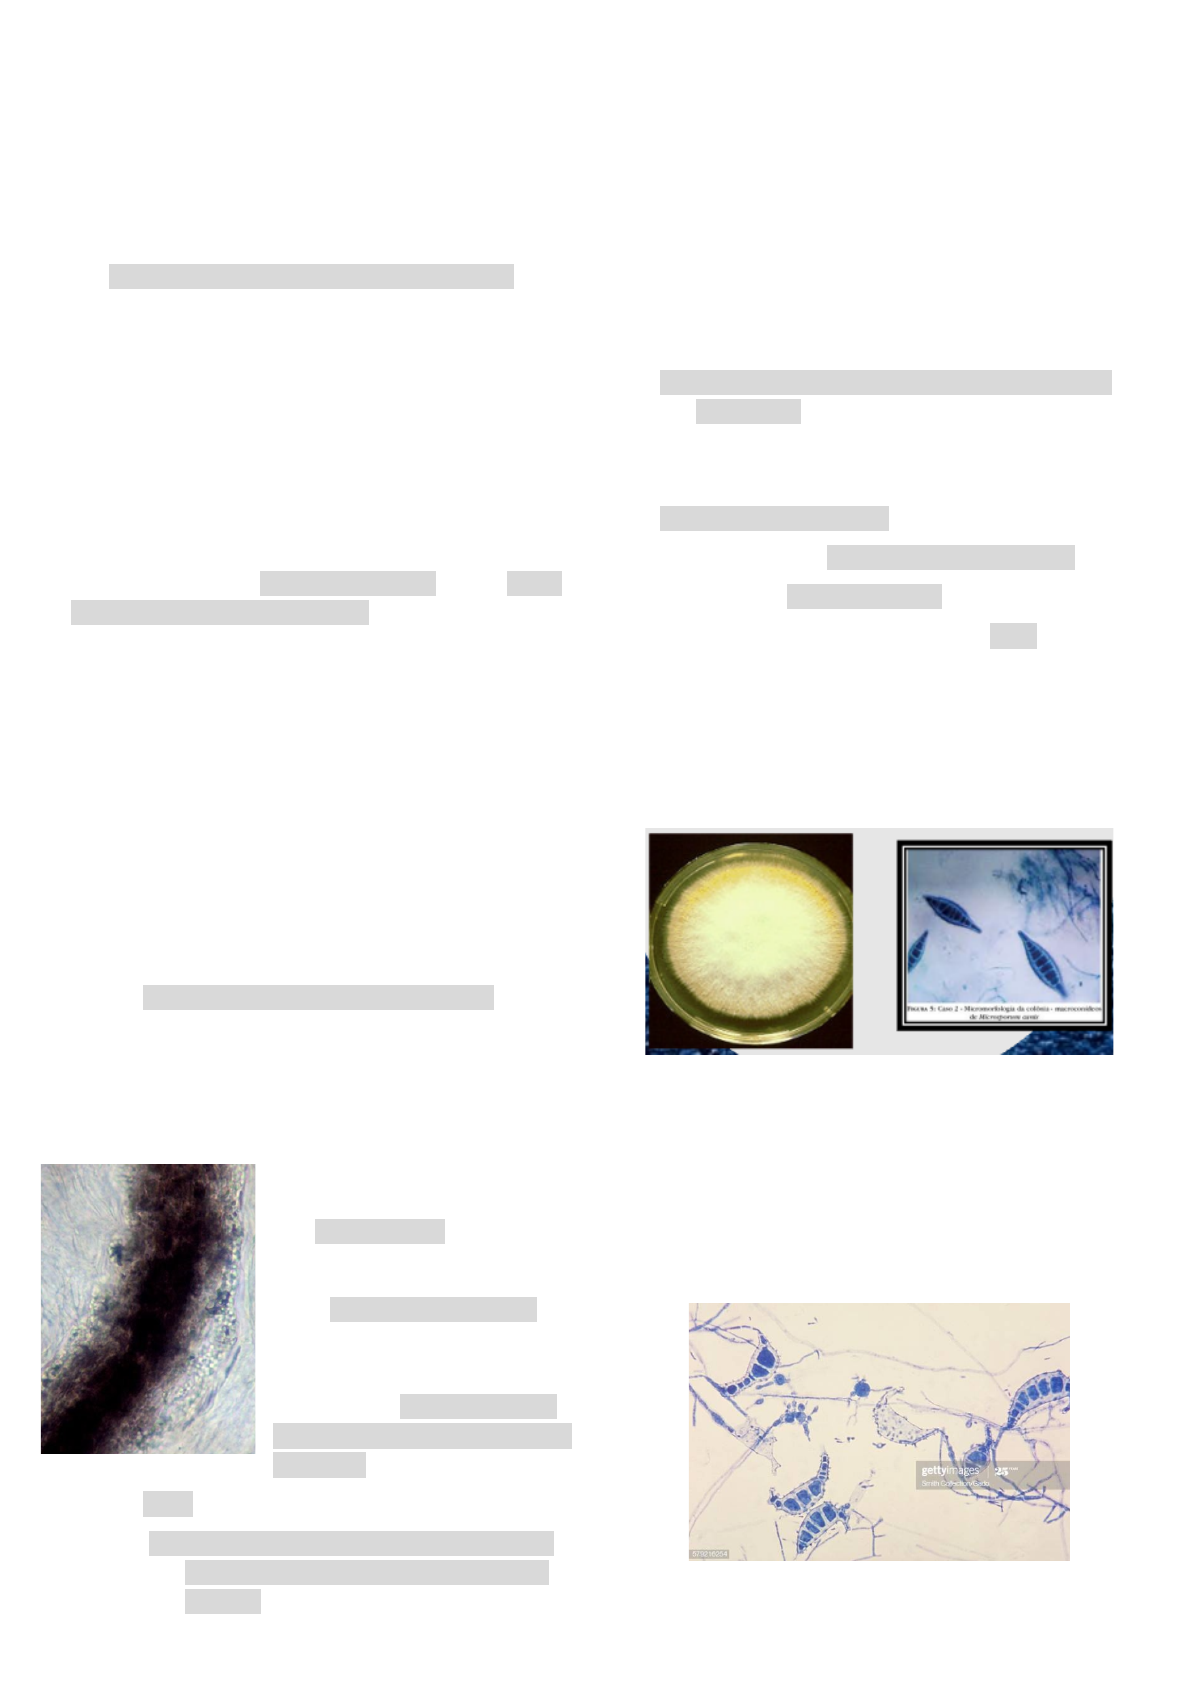

1. Microsporum canis

● colônias: planas, amarelas, reverso amarelo

● Macroconídios: fusiformes e equinulados

● comum em cachorro e gato

3. Microsporum gypseum

● colônias: planas, cor creme, reverso creme

ou amarelo, aspecto pulvurulento (parece

alheia)

● Macroconídios fusiformes

○ Parede fina

○ Apresentam fímbrias